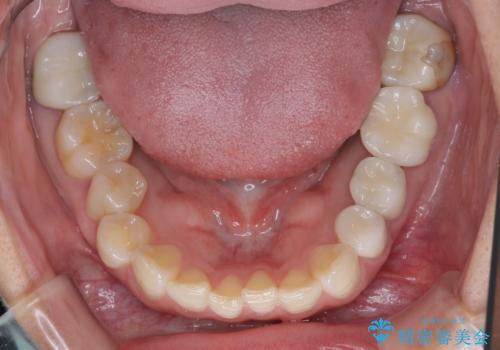

右上の歯は、第二小臼歯の初回処置後に痛みを感じなくなったため、他の歯については問題なしと診断しました。

将来ホワイトニングをされるとのことで、前歯よりもやや白い色合いのオールセラミッククラウンを選択されました。